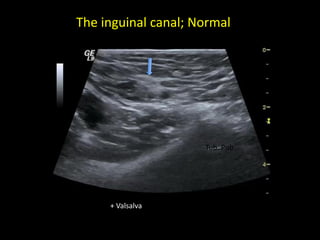

The inguinal canal; Normal

Tub. Pub.

+ Valsalva

The inguinal canal;Normal Tub. Pub. + Valsalva